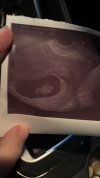

Jest zarodek 1,55 cm i jest serduszko 🥹

Załączniki

• IMG_2710.jpeg

IMG_2710.jpeg

1,9 MB · Wyświetleń: 10